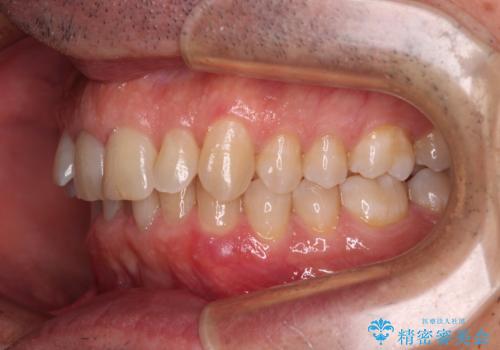

- 前歯のデコボコを気にして来院された患者様です。

インビザラインでもワイヤー装置でも対応可能でしたが、仕事の都合で来院回数を減らしたいとのことでインビザラインによる矯正治療を選択されました。

著しく咬合力が強いため、奥歯がしっかりと噛めずに治療が長引くことが懸念されました。

1セット目のインビザラインを使用した際には左右ともに大臼歯が咬み合っていなかったのですが、2セット目できっちりと仕上げることができました。